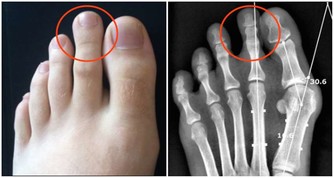

若體內尿酸太多,形成結晶鹽,沉積在腎臟,腎臟長期處在慢性炎症的刺激中,便會功能下降。

腎臟功能一旦受損,排泄廢物(包括尿酸)的能力下降,反過來又會使尿酸水平進一步升高,腎功能進一步受損,形成惡性循環。

不僅如此,沉積的尿酸還可能形成結石,誘發腎絞痛、血尿、腎盂腎炎等。較大的腎結石還可能形成梗阻、腎積水,進一步損傷腎功能。